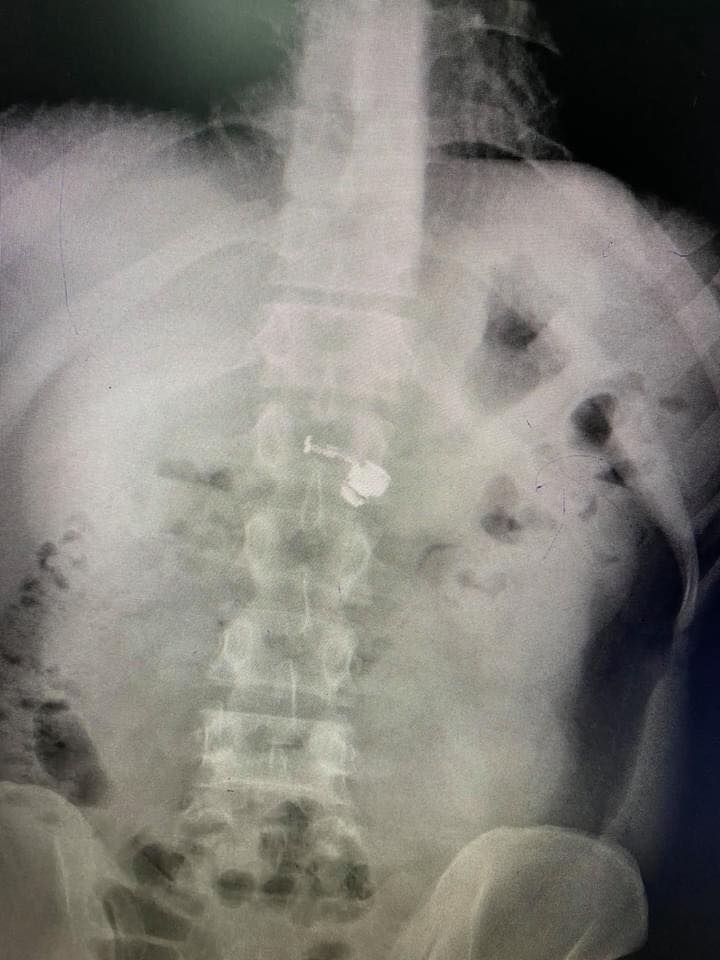

23/04/2021 17:00Video call với bạn gái rồi ngủ quên, sáng ra chàng trai mơ màng nuốt luôn tai nghe AirPods Pro vào bụng một cách 'ngon lành'

Câu chuyện về một chàng thanh niên vô tình nuốt chiếc tai nghe Apple AirPods Pro vào bụng đang thu hút sự quan tâm của cộng đồng mạng.

Nhiều người vừa đọc qua đã thấy rùng mình, theo chàng trai trong câu chuyện, vì lý do vừa thức giấc còn mơ màng nên anh đã nuốt chiếc tai nghe không dây AirPods Pro vào bụng một cách "ngon lành".

"Như tôi vẫn hay kể với các bạn rằng cuộc đời tôi là một chuỗi những câu chuyện bi kịch. Vâng, hôm nay sẽ là một câu chuyện mới: Sáng nay, vào lúc 5 giờ 30 tôi tỉnh dậy thì được mẹ đưa cho nắm thuốc để uống (mẹ hay làm vậy để gọi tôi dậy). Và thế nào đó mà cái AirPods lại đang ở trong tay tôi. Để khiến cho việc này dễ hiểu hơn thì tôi sẽ giải thích thêm, tôi hay video call với bạn gái cả đêm, nên bằng một cách nào đó, trong lúc mơ màng tôi đã vớ lấy cái AirPods đặt vào tay mình. Và chuyện gì đến cũng đã đến, tôi uống đống thuốc mẹ đưa cùng với chiếc AirPods vào bụng, trong lúc đó tôi còn không biết là mình đang mơ hay tỉnh. Còn nghĩ: "Sao đống thuốc hôm nay to thế nhỉ?", cuối cùng tôi đã phải đi phẫu thuật để lấy nó ra", chàng trai kể lại câu chuyện trên một hội nhóm thu hút hàng nghìn lượt tương tác.

Theo đó, Airpods Pro là sản phẩm tai nghe không dây của nhà Apple được nhiều người Việt ưa chuộng bởi các tính năng thông minh vượt trội, thiết kế nhỏ gọn chính là ưu điểm khiến chiếc tai nghe này trở thành thứ mà ai cũng muốn sở hữu. Thế nhưng, bên cạnh những hiệu ứng đặc biệt nó cũng tạo ra vô số rắc rối cho người dùng, ví như chuyện nuốt nhầm tai nghe ở trên không phải là chuyện hy hữu với các tín đồ nghiện Apple trên toàn thế giới.

Đã có nhiều chuyên gia y tế cảnh báo về tình trạng nuốt nhầm "dị vật", cụ thể là tai nghe không dây, thế nhưng trong một giây phút nào đó bất cẩn nhiều người vẫn mắc phải lỗi này. Câu chuyện của chàng trai trên như một lời cảnh tỉnh đến chủ sở hữu của những chiếc AirPods. Ngoại trừ việc nuốt nhầm, người dùng AirPods thường xuyên vẫn có thể bị mắc một số vấn đề về thính giác và phản xạ tự nhiên sẽ không còn linh hoạt như người bình thường.